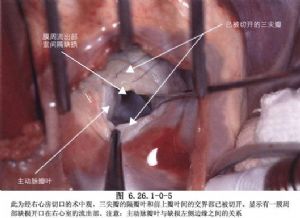

(3)顯露缺損:大缺損尋找比較容易,小缺損有時顯露比較困難,需細心尋找。一般可在三尖瓣隔瓣與前瓣交界附近尋找,將前瓣與隔瓣牽開,膜部缺損四周往往爲增厚的白色纖維環。膜周型缺損位於室上嵴下方,並鄰近主動脈瓣,其前下方爲肌肉緣,缺損常較大,也較多見。

(4)注意傳導束行徑:房室結位於缺損的後下緣肌肉部分,正對三尖瓣間隔瓣和前瓣交界的心房側,希氏束在室間隔缺損後下緣處穿過,此處是手術中最容易損傷的部位(圖6.26.1-1)。